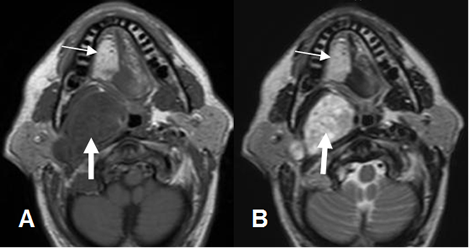

Fig 29 B. Atrofia Muscular.

A: RM axial en T1 y B: RM axial en T2. Gran masa parafaringea derecha, que corresponde a neurinoma. (Flechas gruesas). El compromiso del nervio hipogloso, ocasiona atrofia y degeneración grasa en el lado derecho de la lengua. (Flechas delgadas).